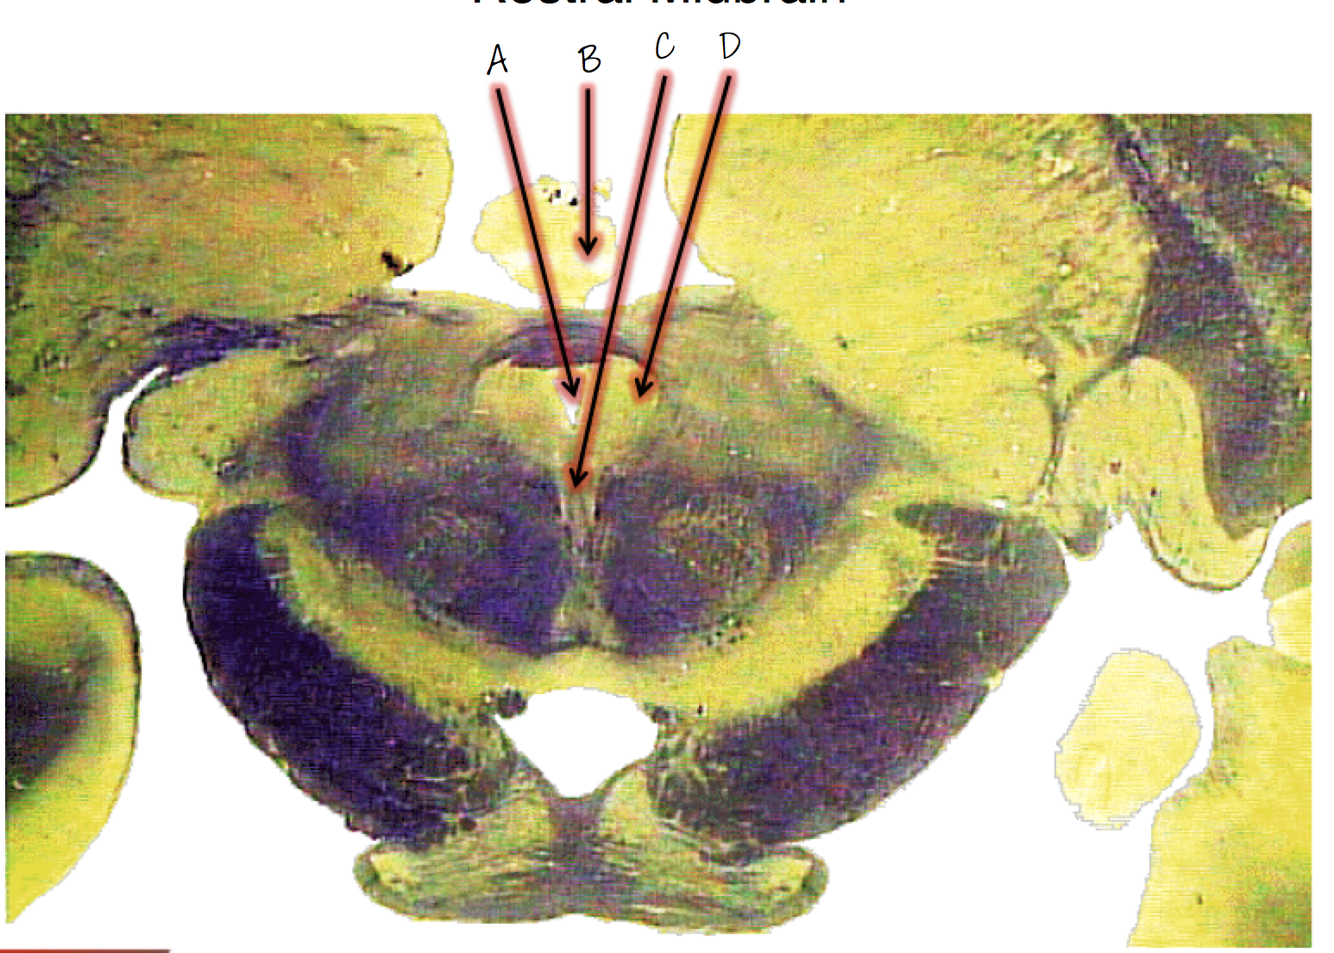

A; cerebral aqueduct

B; pineal body

C; oculomotor nucleus

D; periaqualdutal gray